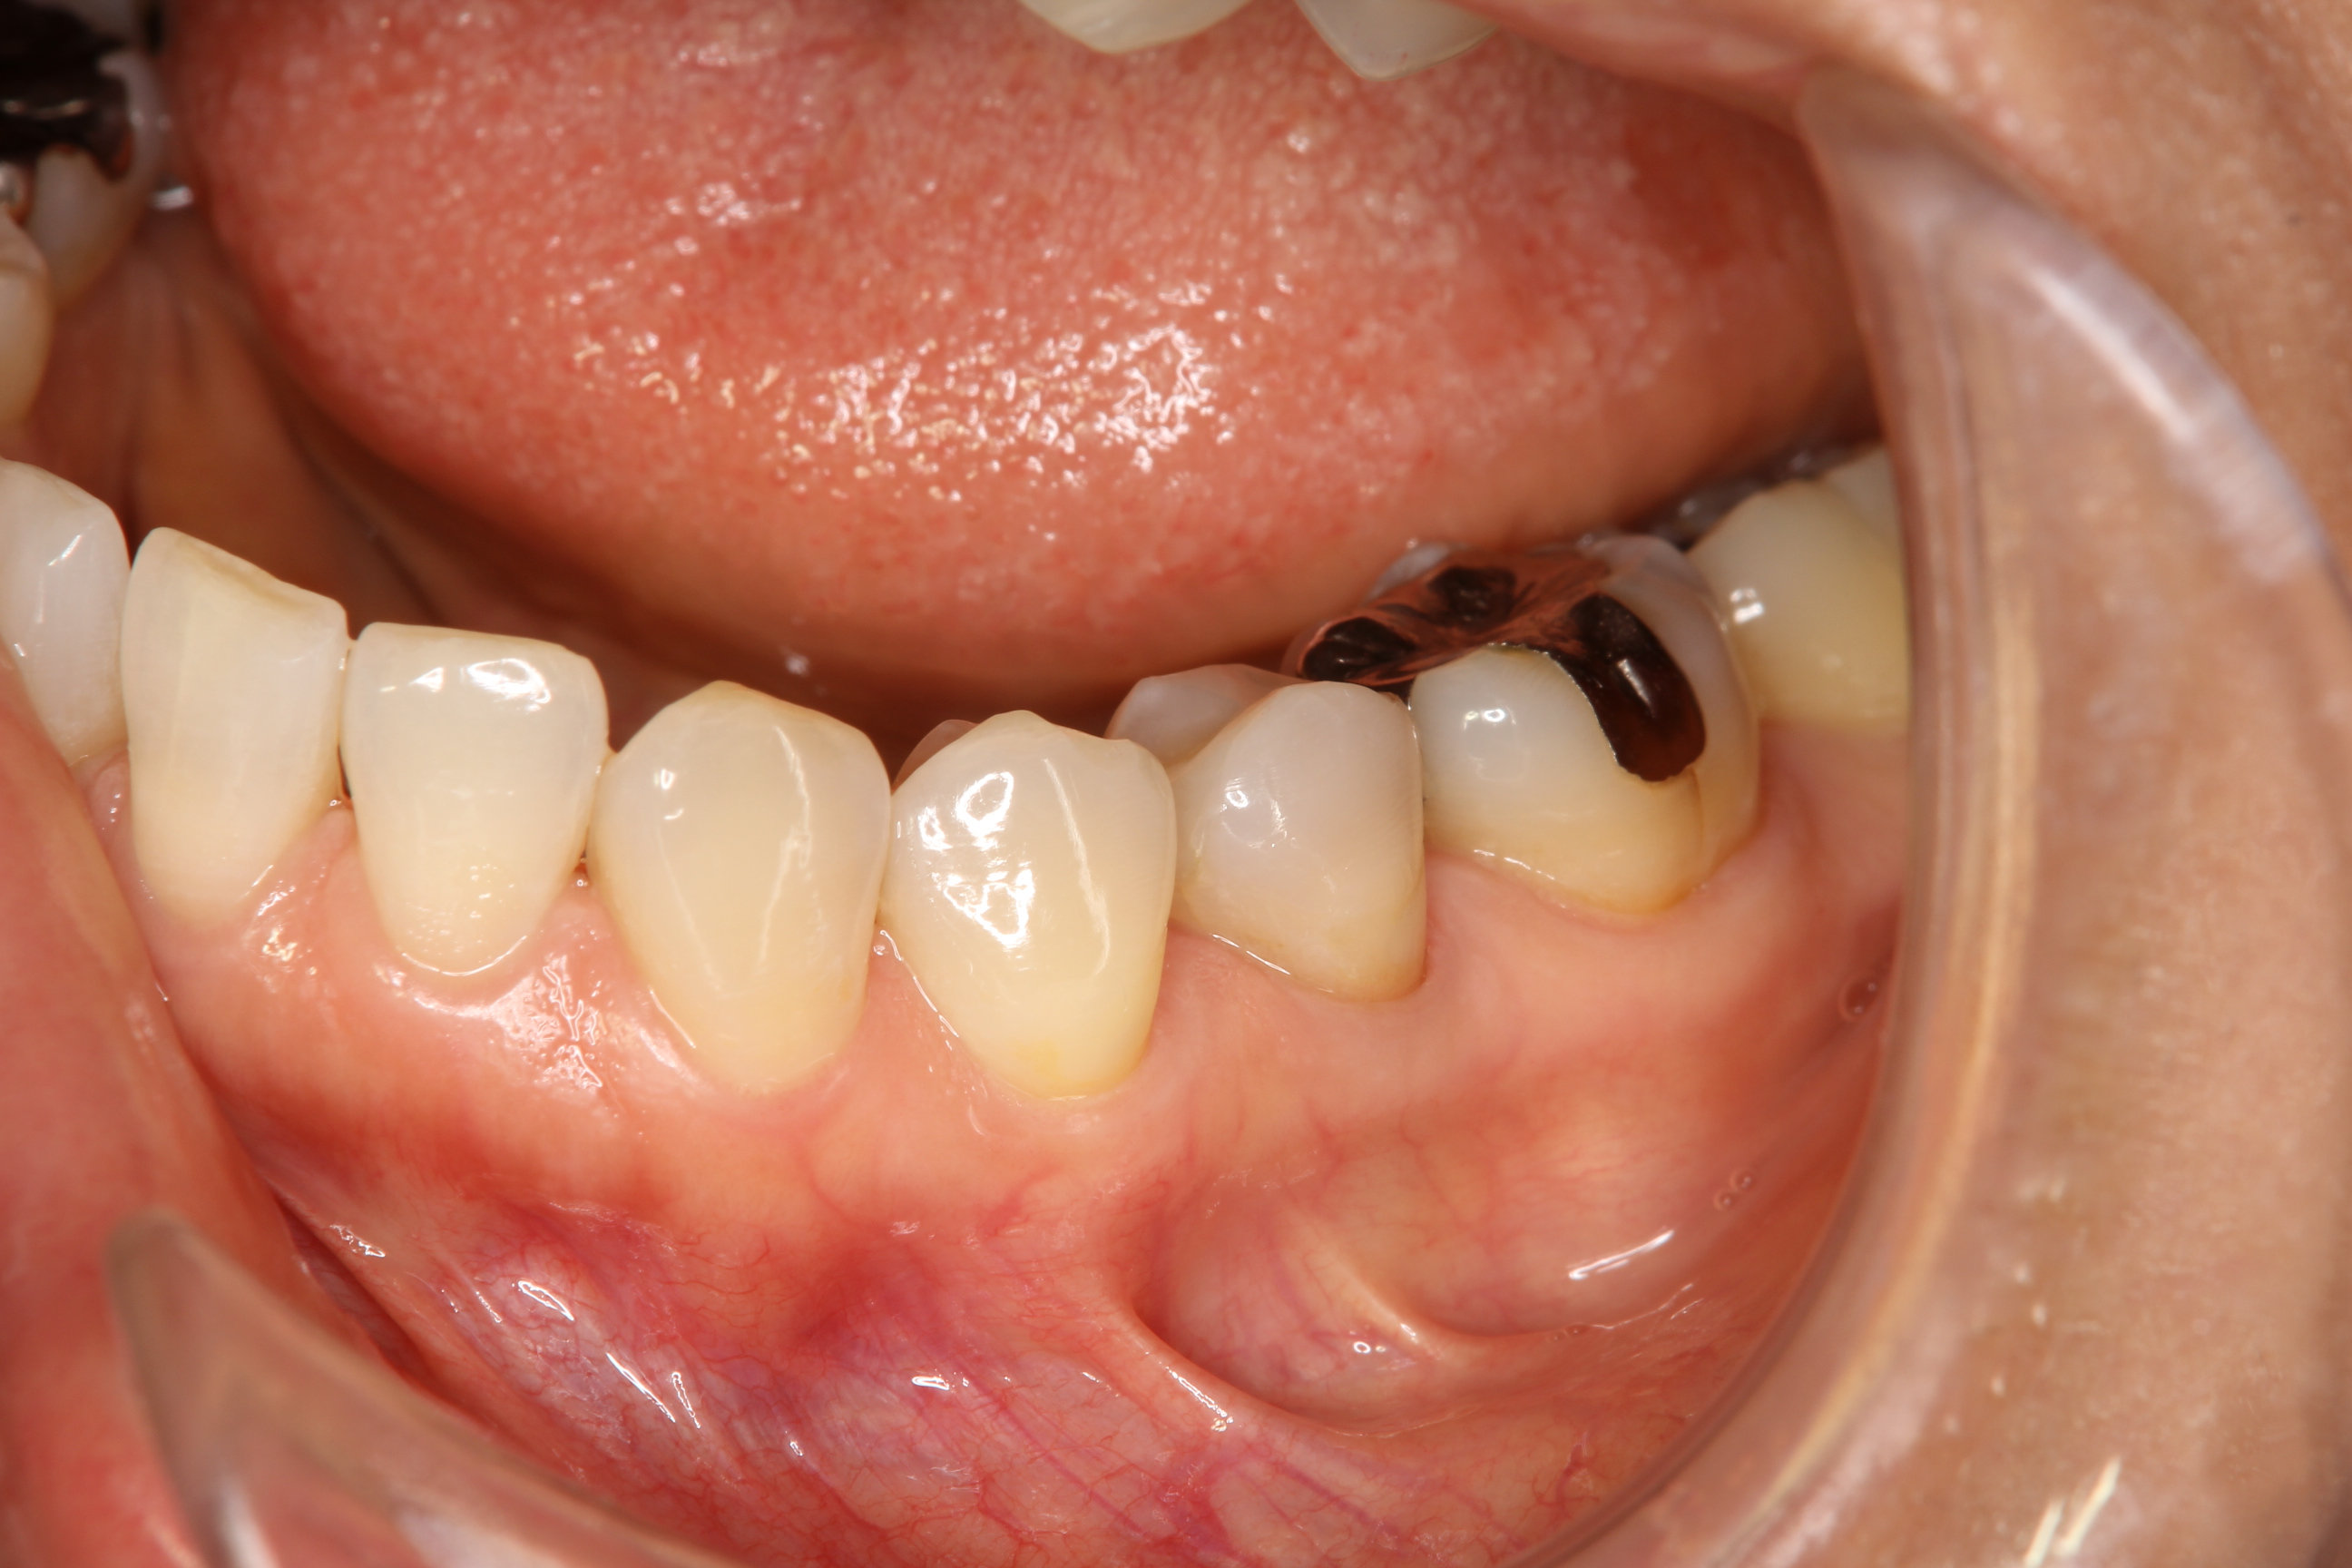

この患者さんは、手前の銀の詰め物が入っている歯に違和感があるということで来院されました。

精査をしてみると、歯と詰め物の間に隙間があり、中で虫歯が進行していました。

ここで、患者さんはセラミックスの詰め物を装着することを希望されたので、シェードテイキングを行いました。

このように、歯の色の見本となるものを入れた状態で写真を撮ります。写真を撮ることで、その場にいない歯科技工士にも正確に歯の色調を伝えることが可能です。